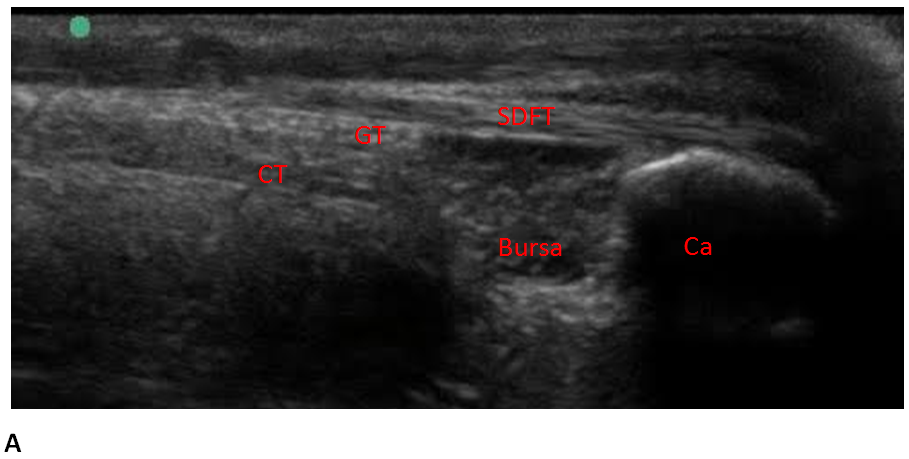

6 7 3 Partial Achilles Tendon Ruptures Ultrasound Cases